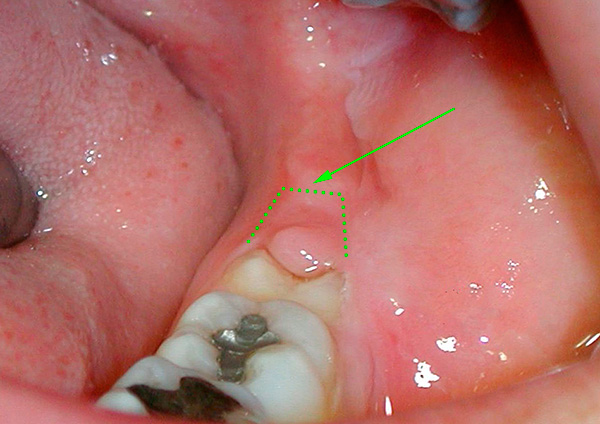

La seguente foto mostra un esempio di un dente del giudizio semi-rinforzato:

Spesso sotto il cappuccio gengivale si accumulano particelle di cibo e batteri, si verifica un processo infiammatorio: la pericoronite. Quando un essudato purulento si forma sotto la gomma, compaiono sintomi che ostacolano la normale vita di una persona: gonfiore nell'area del dente del giudizio, cattive condizioni generali, febbre fino a 38-39 ° C, incapacità di masticare e persino aprire normalmente la bocca, dolore severo, spesso pulsante e irradiante a vari sezioni del viso.